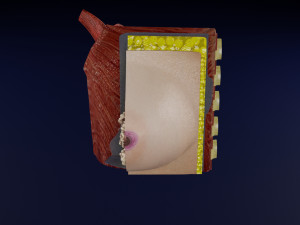

This is a 1:1 scaled model of right breast cut opened in sagittal plane to reveal its internal antomy and histology (schematic). The deeper parts and fascial layers are also depicted to give a very detailed approach to the model. The full layers starting from skin, nipple areola, till intercodtal muscles and ribs are also depicted.